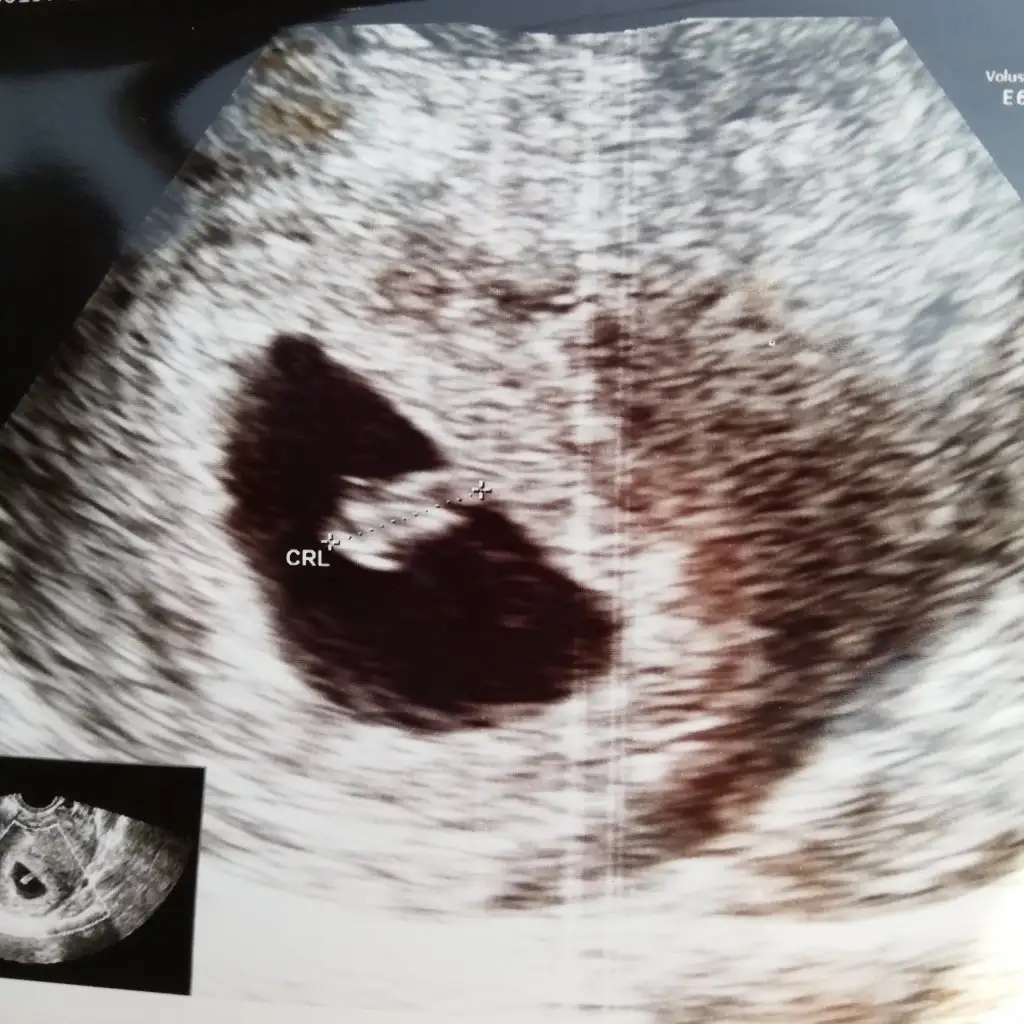

Gözün aydın canım çok seviniyorum böyle mesajlar okuyuncaMerhaba kızlar bugün randevum vardı rahim arkaya dönük olduğu için karından çok net gözükmedi, vajinal bakıldı haftasıyla uyumlu 7 haftalık dedi kaalp atışı da duyuldu çok şükür bir problem yok bulantı ilacı verdi ama dakikada kalp atış hızını sormayı unuttum ben heyecandan :)